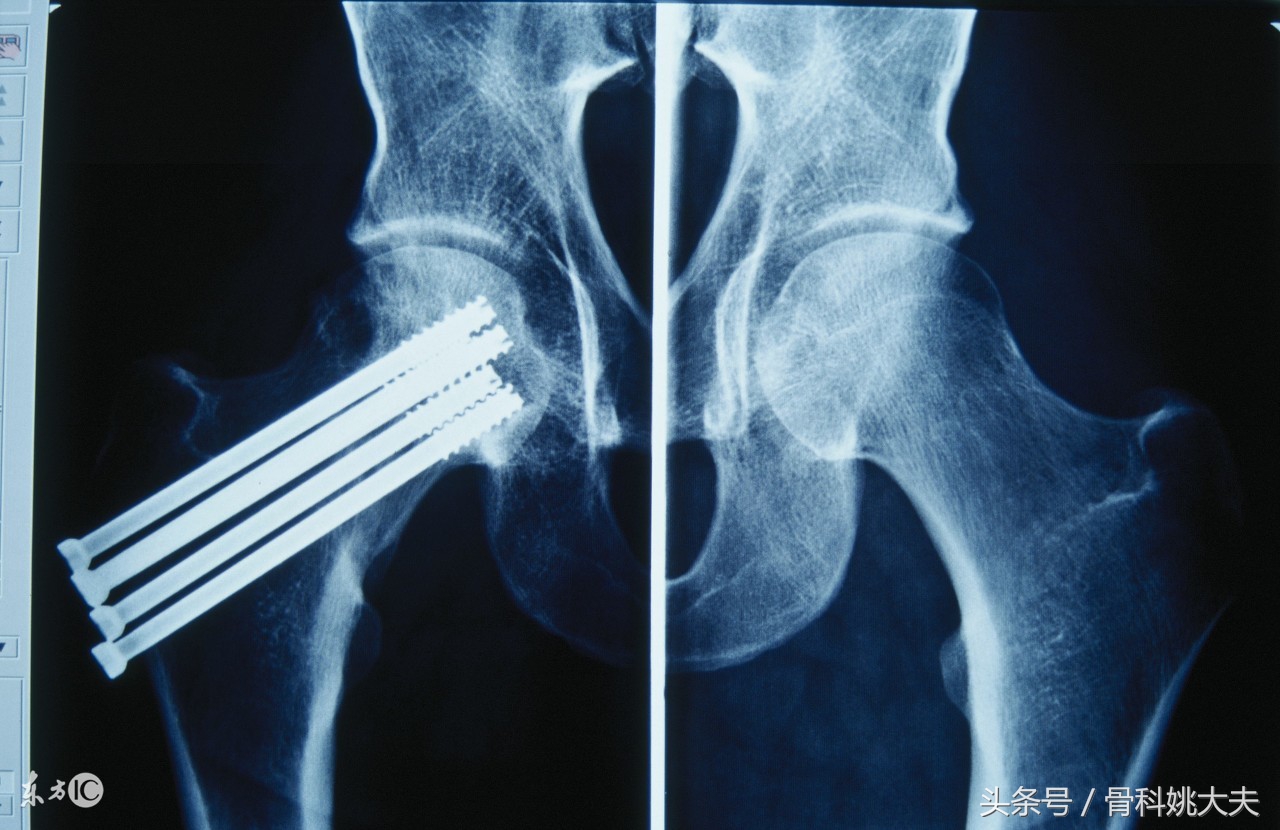

5.骨折部位 肱骨中下1/3,胫骨中下1/3 股骨颈骨折 舟骨骨折,距骨颈骨折等部位骨折愈合困难